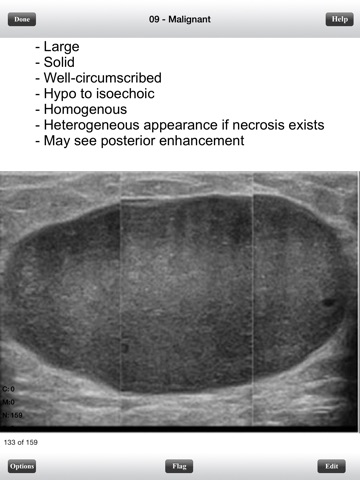

Malignant - 159 flashcards